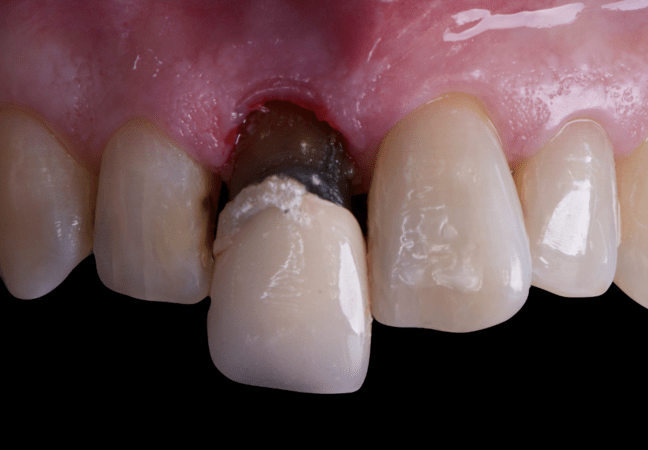

The surgical protocol began with the atraumatic extraction of tooth 1.1 to preserve as much of the alveolar socket as possible. Immediately following extraction, an N1 implant was placed into the socket using a guided surgical approach to ensure ideal three-dimensional positioning. The “one abutment one time” technique was applied to minimize soft tissue manipulation during the healing phase, which is particularly important in esthetic areas.

Given the significant buccal defect, guided bone regeneration (GBR) was performed simultaneously. A mixture of autologous bone and creos™ xenogain™ was applied to the defect and covered with a resorbable creos™ membrane to restore ridge width and support the buccal contour. In addition, a connective tissue graft was harvested and placed in the vestibular region to increase the thickness of keratinized mucosa. This combined approach addressed both hard and soft tissue deficiencies, providing the biological foundation for a stable and esthetic outcome.

On the same day as the surgery, an immediate-load provisional crown was delivered. This restoration was fabricated in acrylic resin and screw-retained on the implant, following the “one abutment one time” principle. The provisional crown was carefully adjusted to avoid occlusal loading while supporting the peri-implant soft tissue architecture during the healing phase.

The provisional not only satisfied the patient’s functional and esthetic demands but also played a key role in shaping the emergence profile and conditioning the gingival margin. By providing a provisional solution immediately, the patient was able to leave the clinic with a natural-looking smile, avoiding any psychological or social impact associated with tooth loss in the anterior maxilla.